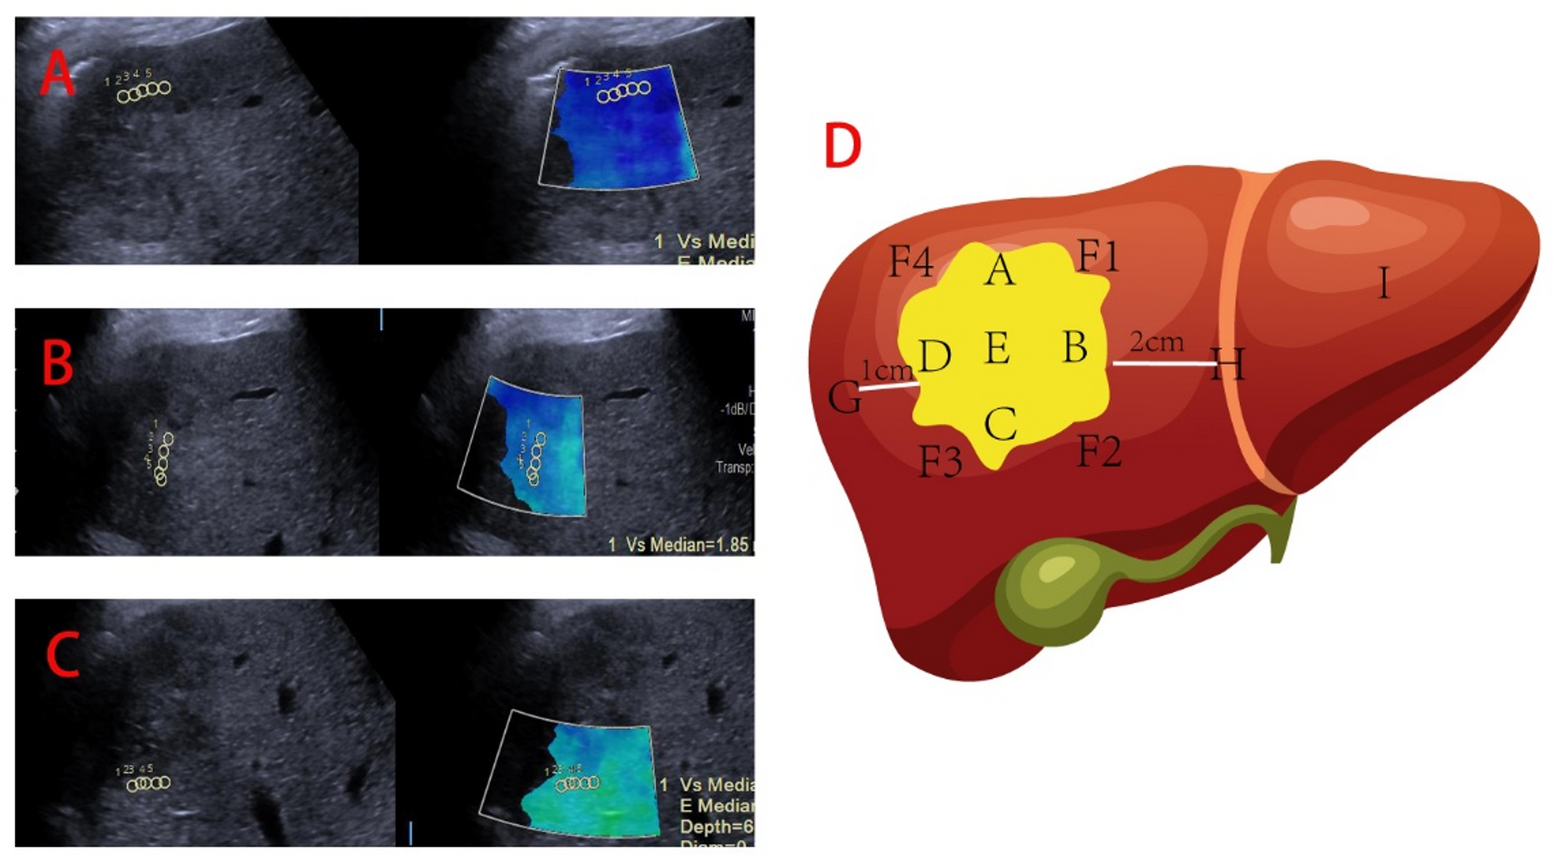

Fig. 2

Diagrams illustrating tumor stiffness measurements (A) demonstrates measuring the stiffness in front of the tumor, (B) shows measuring the stiffness on the left side of the tumor, (C) indicates measuring the stiffness at the bottom of the tumor, and (D) depicts the positions for measuring tumor stiffness, including the anterior, posterior, left, right, and middle (ABCDE) of the tumor parenchyma, the stiffness of the liver tissue in the four quadrants adjacent to the tumor parenchyma (F1, F2, F3, F4), the tissue stiffness one centimeter from the tumor edge (G), two centimeters from the tumor edge (H), and the stiffness of normal liver tissue (I).